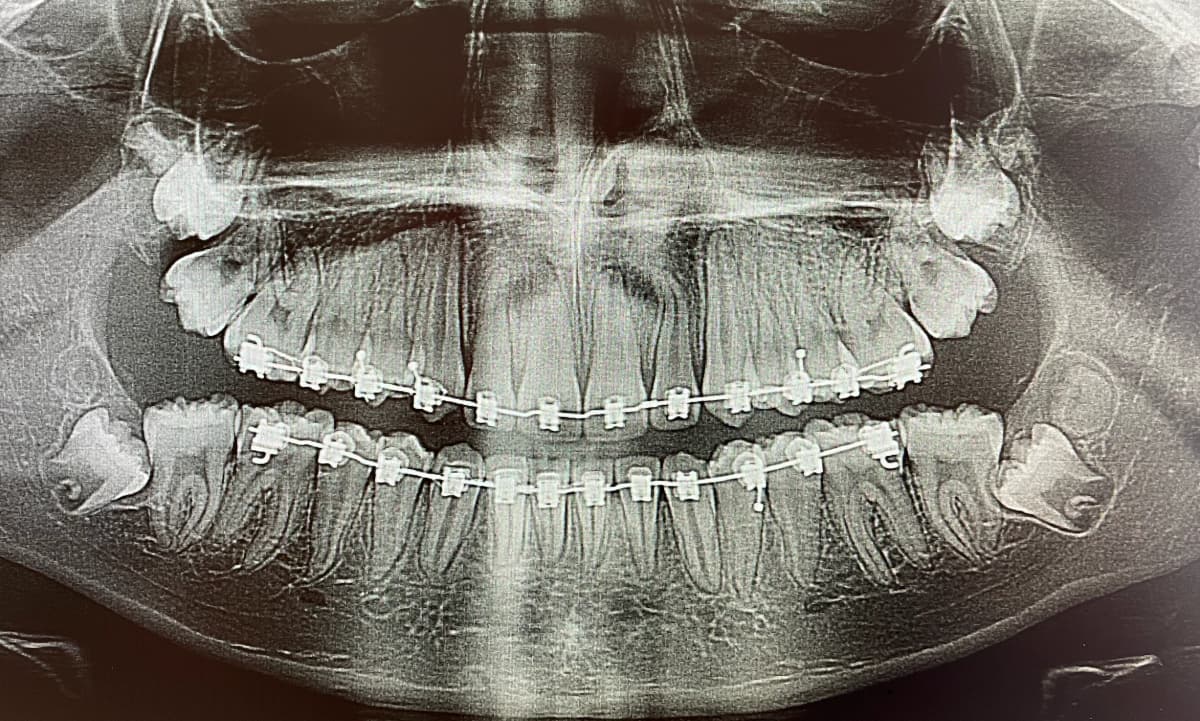

L'extraction des dents de sagesse, également appelées troisièmes molaires, est une procédure dentaire courante effectuée pour enlever les dents qui ne peuvent pas pousser correctement ou qui causent des problèmes dentaires. Elles sont généralement du nombre de quatre et font habituellement leur apparition en bouche entre l’âge de 15 et 25 ans. Elles peuvent faire complètement éruption, être partiellement éruptées ou incluses. Elles n’ont généralement pas assez de place dans la bouche. Ce faisant, elles sont très souvent mal alignées et exercent des pressions sur les dents adjacentes, pouvant même les endommager. L'extraction des dents de sagesse est souvent recommandée lorsque les dents sont incluses (piégées dans la gencive ou l'os) ou qu'elles causent des problèmes tels que la douleur, l'infection, la carie dentaire, le déplacement des autres dents ou le développement de kystes. Il est conseillé de procéder à leur extraction à un jeune âge, généralement à la fin de l’adolescence ou au début de l’âge adulte. Effectivement, les risques s’accroissent avec l’âge et la convalescence est plus aisée à un jeune âge.